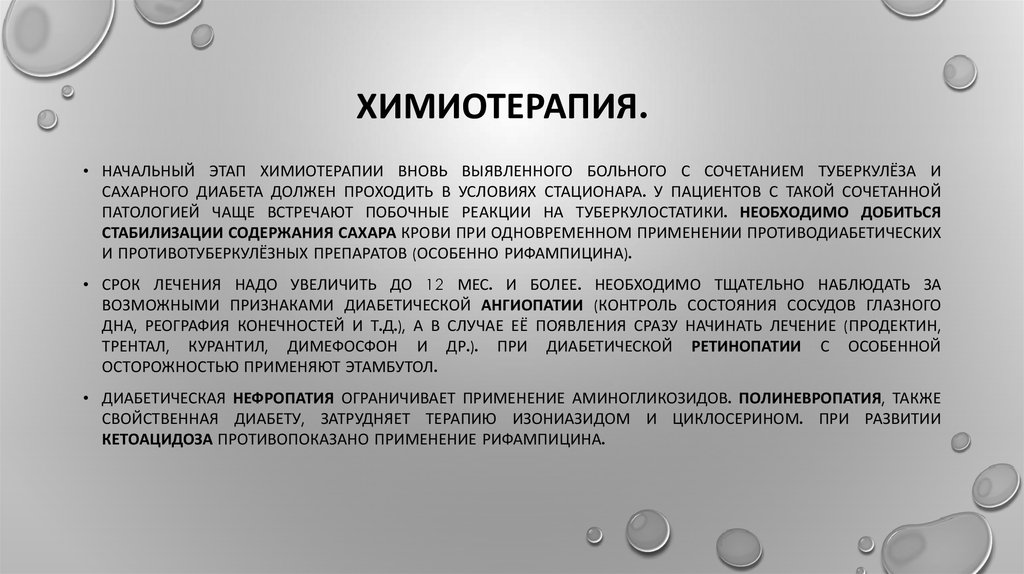

Лечение туберкулеза: Методики химиотерапии

Раздел: Визуальный дайджест